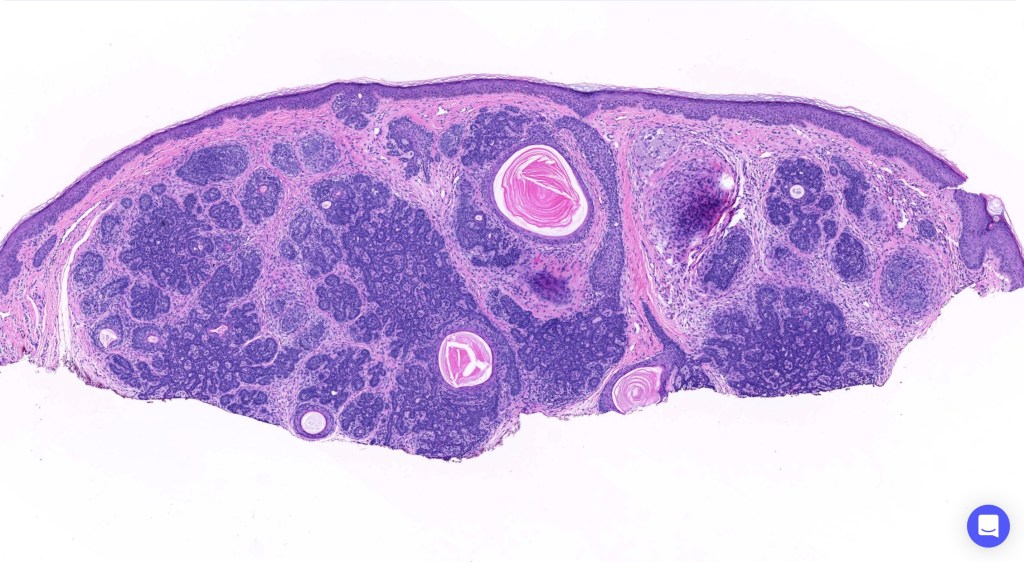

Trichoepithelioma is a hamartoma comprising a basaloid/germinative component and a prominent perifolliclular sheath proliferation. It may present as a solitary lesion or as multiple, familial lesions in multiple familial trichoepithelioma (which is probably a variant of Brook-Spiegler syndrome) & Brook-Spiegler syndrome.

•The classical appearance consists of keratocysts & lobules of basaloid cells

•Some tumors are devoid of keratocysts

•Perifollicular mesenchyme is always conspicuous and sometimes densely aggregated are seen indenting the baslaloid lobules (papillary mesenchymal bodies)

•Amyloid, foreign body granuloma formation to free keratin & calcification are variable features

Trichoepithelioma should be distinguished from trichoblastoma since the latter is very rarely syndromic. Trichoepithelioma is largely a dermal tumor whereas trichoblastoma often extends from the dermis into subcutaneous fat or deeper in very large examples. Papillary mesenchymal bodies are much better formed and generally more obvious in trichoepithelioma. Trichoepithelioma must also be distinguished from basal cell carcinoma. Retraction artifact & stromal mucin are features of basal cell carcinoma and not trichoepithelioma. Papillary mesenchymal bodies are not seen in basal cell carcinoma.